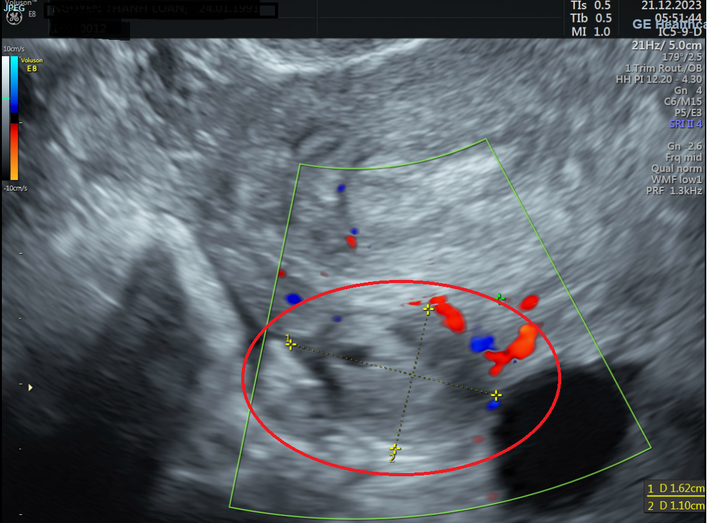

BSCKII Đỗ Văn Tú (Trưởng khoa Sản Phụ khoa - Bệnh viện Đa khoa Hồng Ngọc Yên Ninh) cho biết: “Khi siêu âm, chúng tôi không thấy hình ảnh phôi thai trong buồng tử cung dù trước đó chị L. tự thử thai cho kết quả 2 vạch. Nhưng các bác sĩ lại thấy tại buồng trứng trái của bệnh nhân có khối kích thước 10x13cm, nghi ngờ thai ngoài tử cung, có khả năng phải phẫu thuật bỏ thai, tránh nguy hiểm đến tính mạng của mẹ.”

Hình ảnh siêu âm cho thấy tại buồng trứng trái có khối KT: 11x15 mm nghi ngờ thai ngoài tử cung.